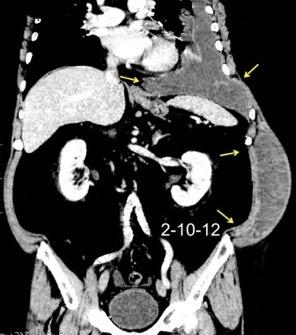

Comunica con el hiato esofágico y el espacio pararrenal anterior.

Colecciones “inflamatorias” abdominales llegan al tórax vía el hiato esofágico o por vía transdiafragmática

Afectación transdiafragmática: 5,6-43,7% de quistes hepáticos. “Área desnuda” del hígado.

Panda A et al. “Straddling Across Boundaries”. Thoracoabdominal Lesions: Spectrum and Pattern Approach. Curr Probl Diagn Radiol. 2015 Área desnuda. El hígado en contacto directo con el tendón central del diafragma. Contiene el hiato de VCI.